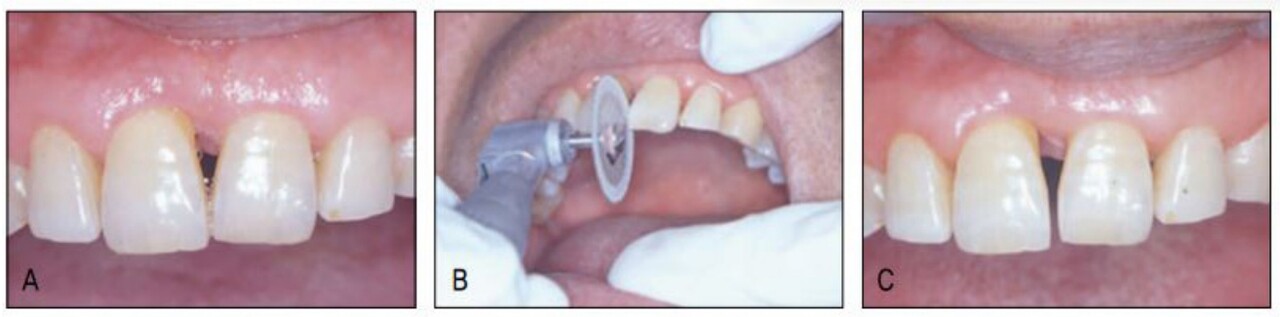

그러나 전치부 과개교합으로 상악설측면에서의 장치 부착이 불가하여 환자에게 투명교정장치를 설명하였고 이 역시 심미적 장치이어 환자가 수락하고 투명교정장치로 간단하게 공간클로져 교정을 시행 하였다. 가철식 장치이어서 다소의 경사이동이 발생하였고 치주질 환으로 우측의 중절치가 더 정출하여 비심미적인 절단연이었으나 스트리핑 그리고 re-shaping 등을 이용하여 심미적인 절단연을 만들어주었다. 교정을 주저하였던 환자는 설측및 투명장치 등 심미적 장치로 인해 교정치료 내내 크게 만족해 하였다(그림 23-7~10).